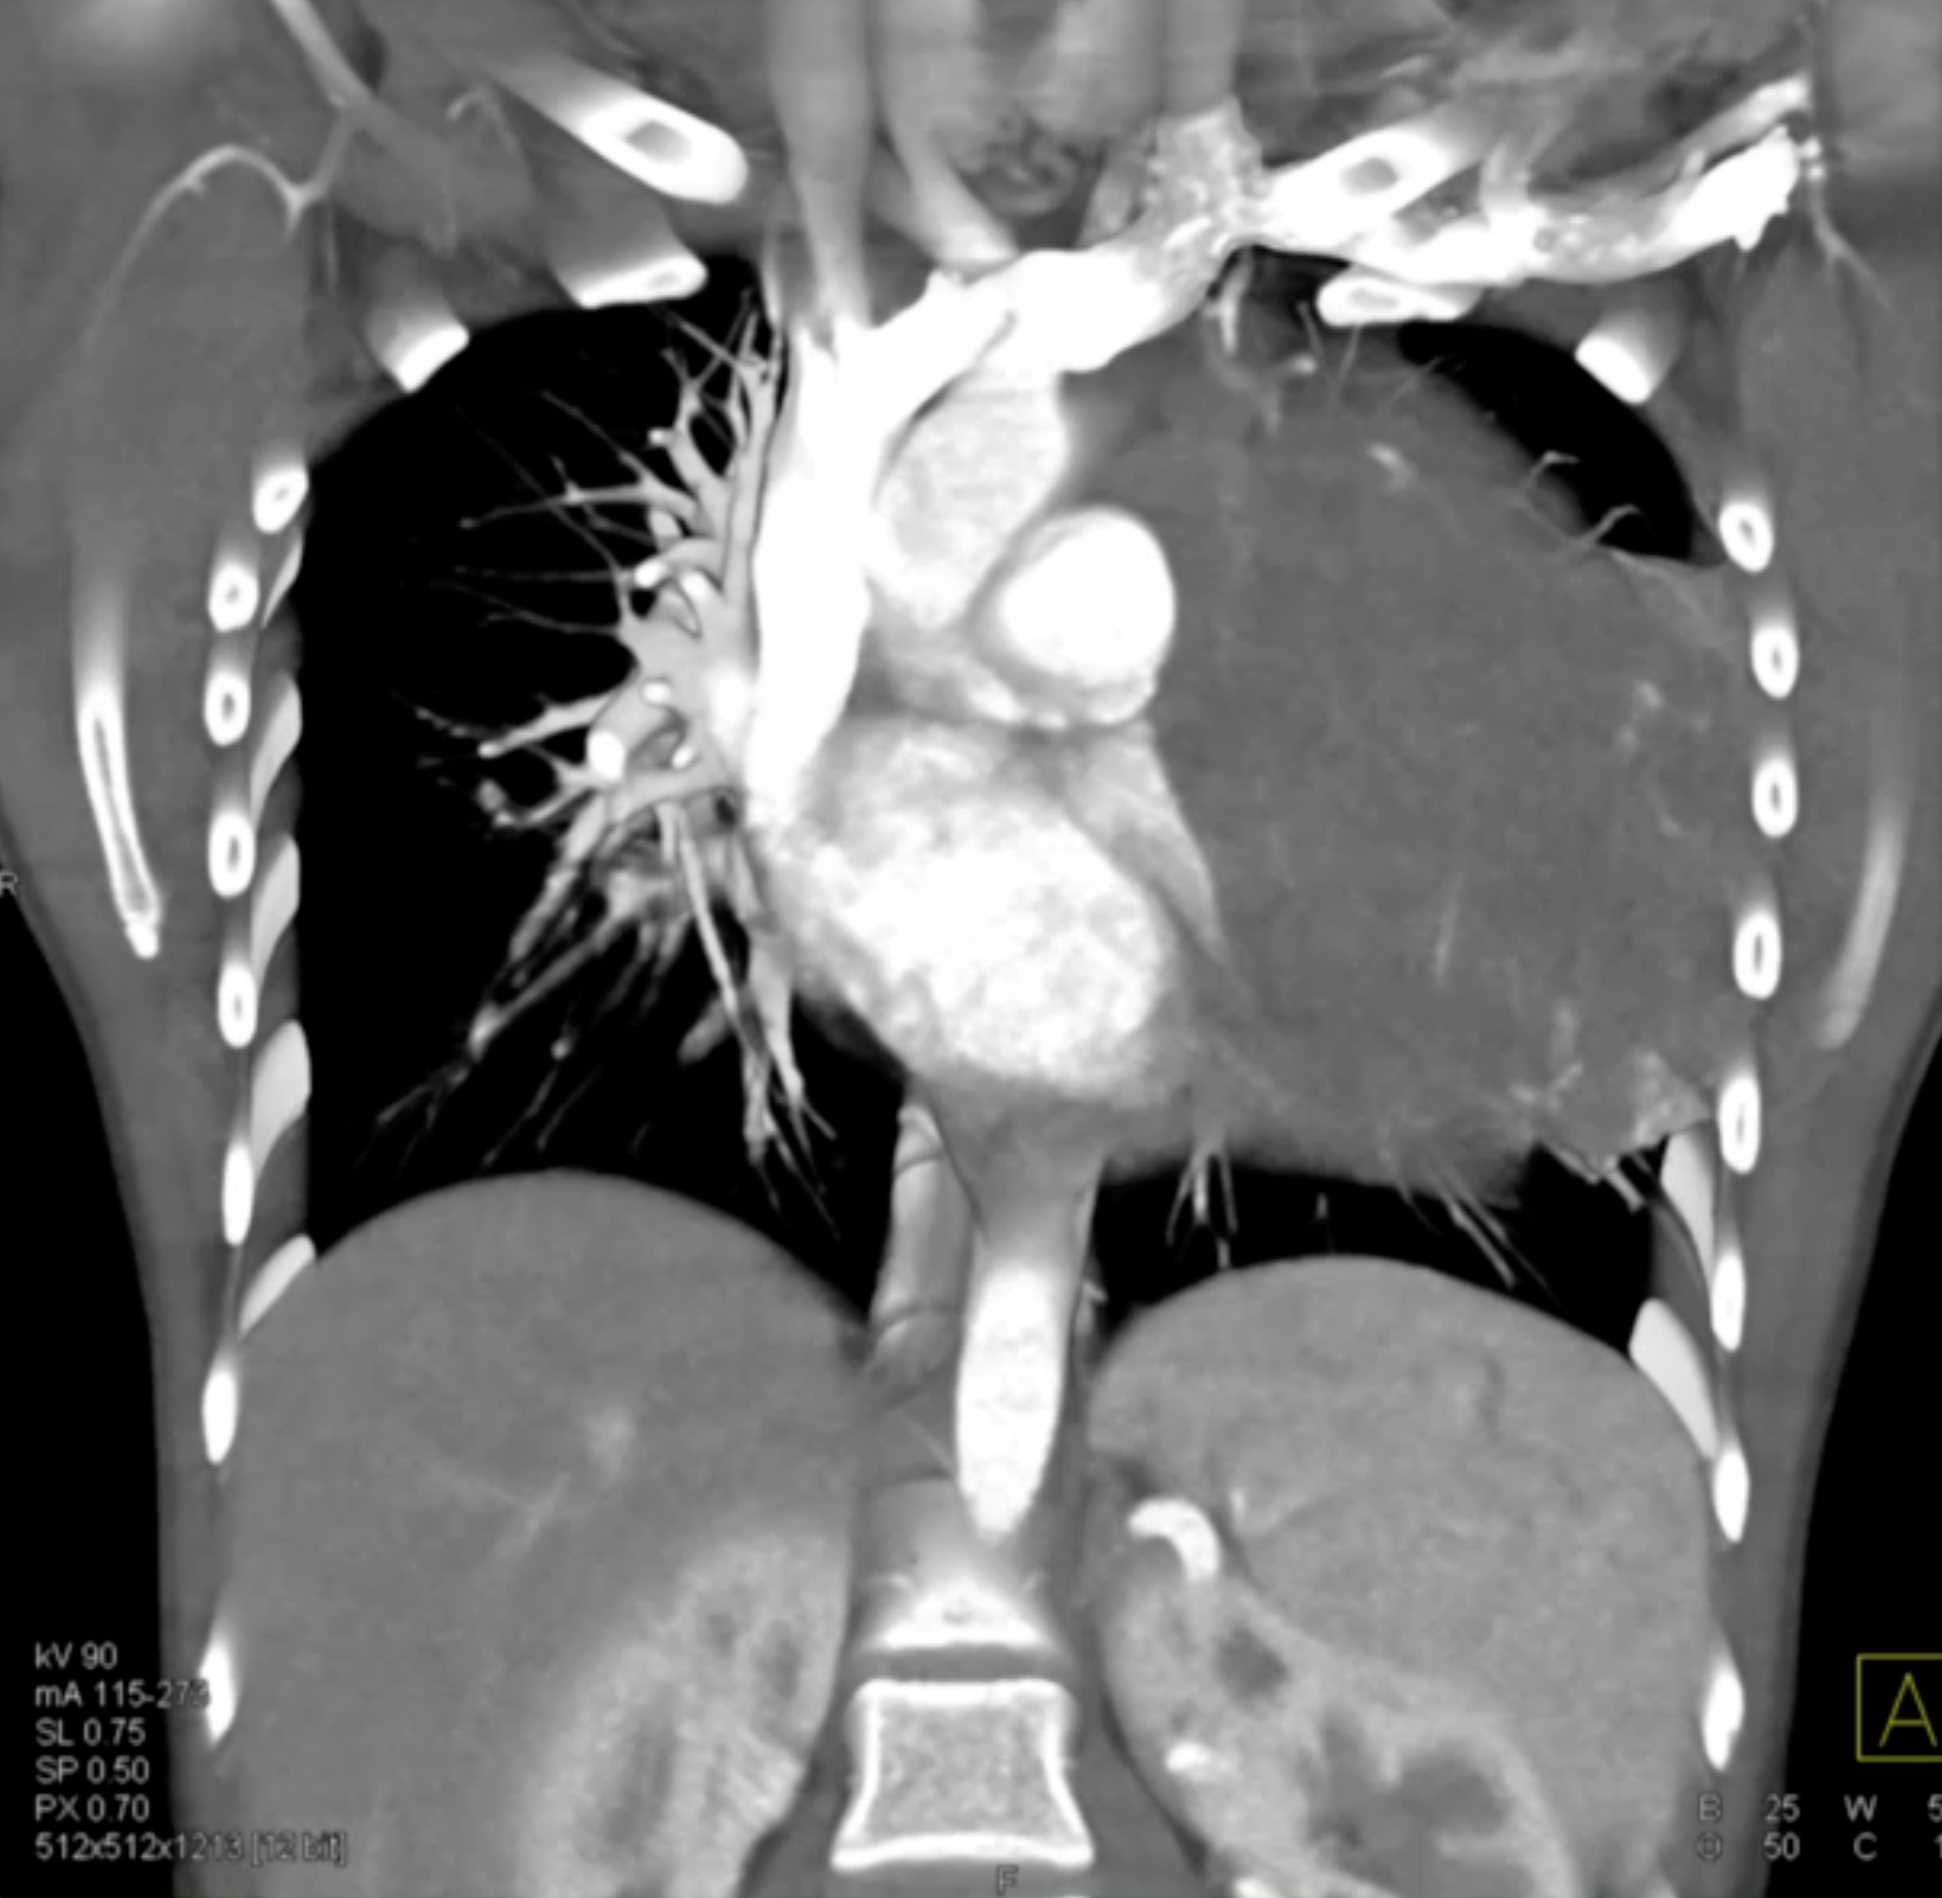

Subtle Adenocarcinoma Pancreas